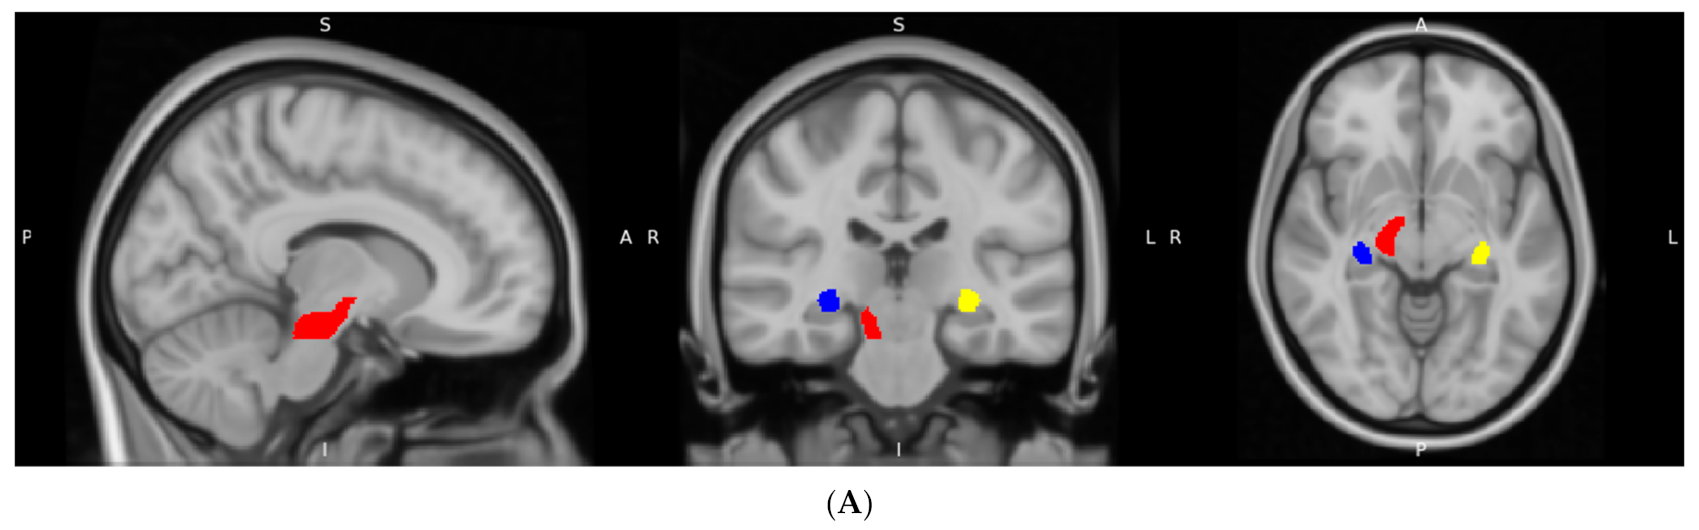

Figure 3.

WM regions with significant differences in FA and MD values. (A) regions with significant differences in FA (red: right CP; yellow: left FX/ST; blue: right FX/ST) (B) regions with significant differences in MD (red: left FX/ST; yellow: right CST; blue: right ICP).

As shown in Table 2, extensive differences were observed in these metrics between the TCC group and the control group. With regard to the FA metric, it was found that there were statistically significant differences in three distinct regions (Figure 3A): the right cerebral peduncle (CP) (F = 4.578, p = 0.039), right fornix (FX)/stria terminalis (ST) (F = 4.606, p = 0.038), and left FX/ST (F = 4.909, p = 0.033). However, after taking age and education as confounders into account, the significance of FA alternations became marginal.

The study also identified that the TCC group significantly differed from the control group in MD in the right corticospinal tract (CST) (F = 6.625, p = 0.014), right inferior cerebellar peduncle (ICP) (F = 6.045, p = 0.019), and left FX/ST (F = 5.070, p = 0.030) (Figure 3B). Specifically, the TCC group demonstrated lower MD values in the left FX/ST region compared to the control group. In contrast, the TCC group exhibited higher MD values in the right CST and the right ICP relative to the control group.